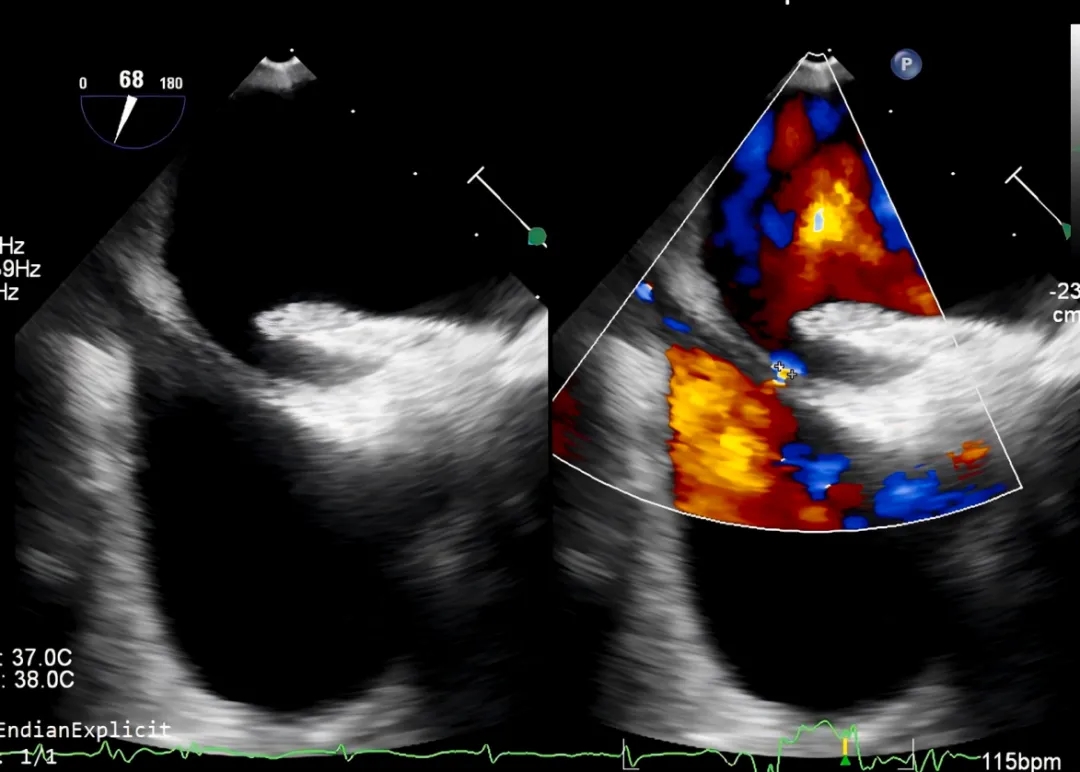

一名52岁女性患者因卵圆孔未闭封堵术20个月后出现头痛及卒中复发而就诊。20个月前,该患者曾因卵圆孔未闭相关脑梗死,于当地医院使用18mm陶瓷膜涂层的房间隔缺损封堵器(先健科技(深圳)有限公司)行卵圆孔未闭封堵术。入院后,患者接受了经食管超声心动图及经食管右心声学造影检查(图1)。超声结果显示封堵器贴合不良,其下缘存在2mm残余右向左分流,右心声学造影进一步证实存在显著的残余分流。

图1 二次干预手术前经食管超声心动图检查

经食管超声心动图显示原封堵器盘面贴合不全、内皮化不完全,封堵器下缘可见一处2mm的右向左分流。